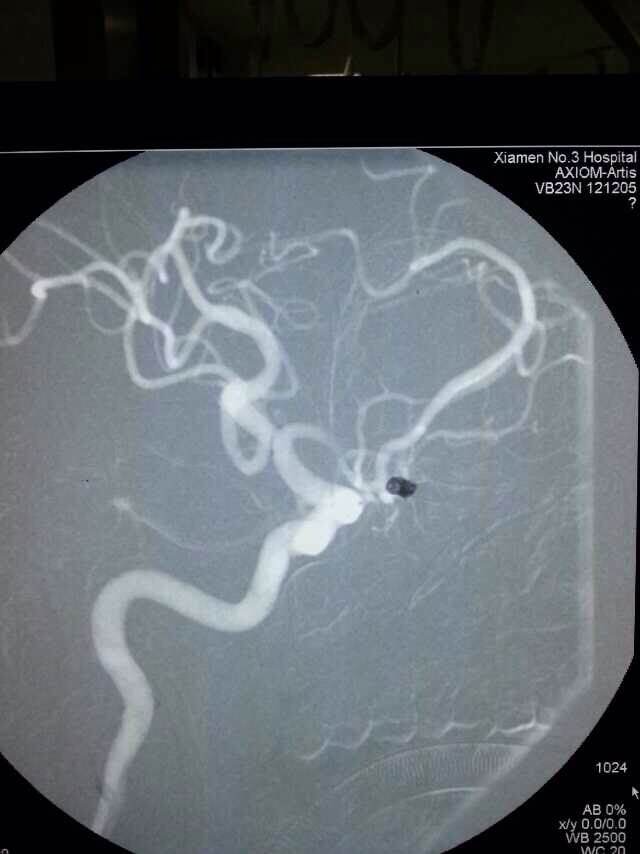

2014520是个特别的日子,第三伦理片 手术室灯火通明,神经外科调集所有的技术团队手术一台接一台,有脑动脉瘤破裂的,有脑外伤出血的,忙碌不停。